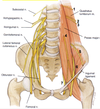

Upper attachments of the psoas major

- Sides of vertebrae T12 to L5

- IV discs

- Transverse processes

Lower attachment of the psoas major

Lesser trochanter of the femur with iliacus muscle (iliopsoas)

Posterior abdominal wall muscles that cross under the inguinal ligament

- Psoas major

- Iliacus

Upper attachments of the iliacus

- Superior 2/3 of iliac fossa

- Ala (wing) of sacrum

- Anterior sacroiliac ligaments

Lower attachment of the iliacus

Tendon of psoas = iliopsoas

5 muscles of the posterior abdominal wall

- Psoas major

- Psoas minor

- Quadratus lumborum

- Iliacus

- Transversus abdominus